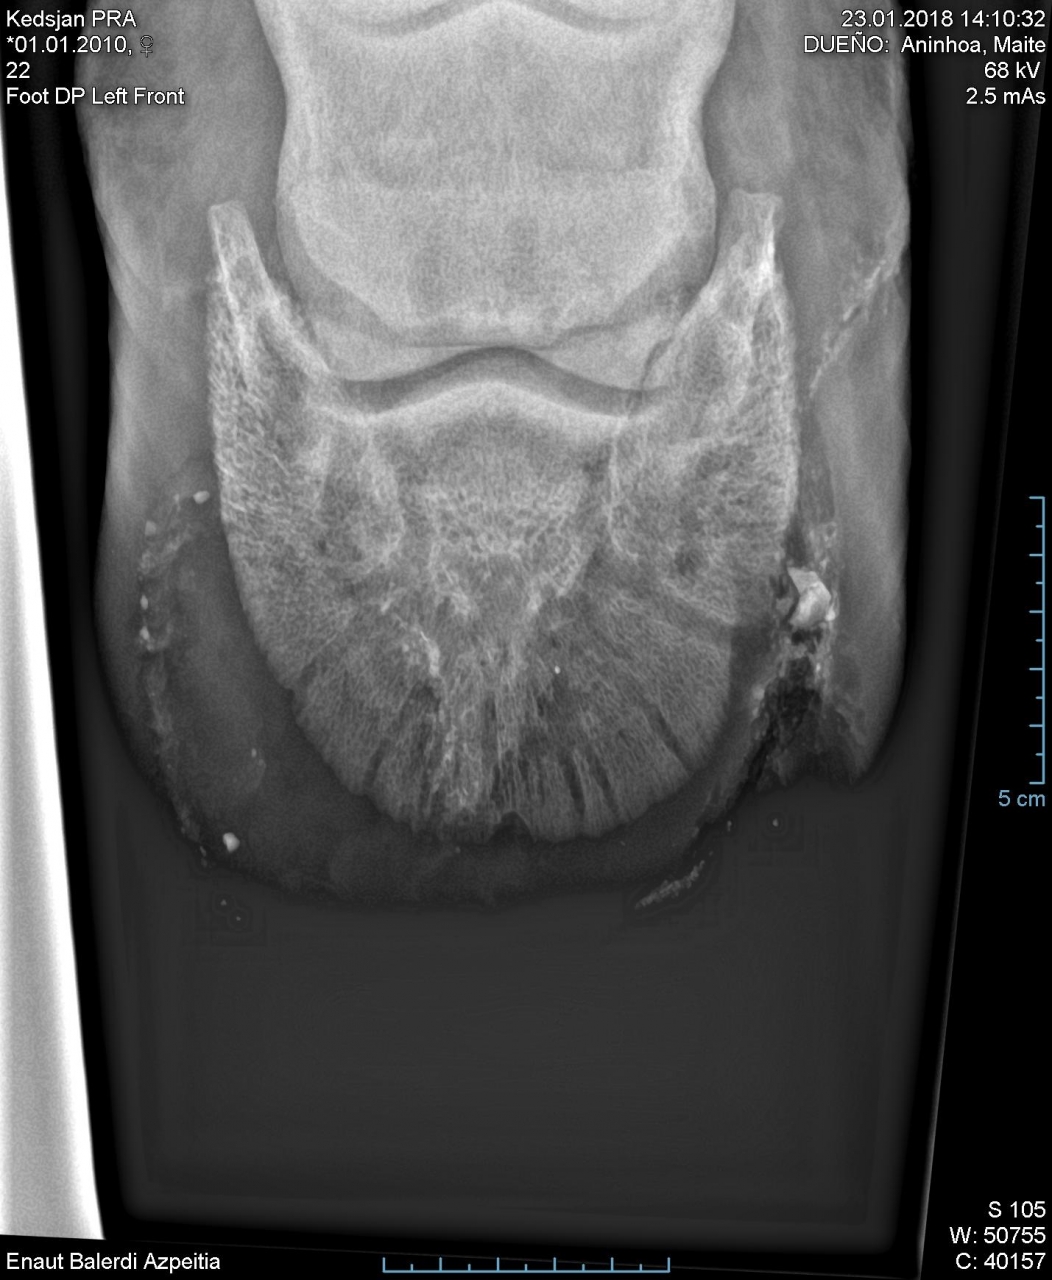

| Dire merci | Bonjour Quelqu'un aurait il déjà eu ça dans le pied de son cheval ? 2 veto sèchent sur ce que ça pourrait être... Jument archi boiteuse et réagissant à la sonde là où ce trouve cette chose. Mais qu'est ce que c'est et d'où ça vient ? Mon veto habituel à soumis les clichés à une clinique vétérinaire, on attend leur avis. Merci ![]() ![]() ![]() |

| Dire merci | Le truc rond c'c'est le veto qui a creusé car on pensait à un abcès au départ, c'est la petite tâche juste au dessus qui nous pose problème... seera oui tu peux partager |

| Dire merci | Pour moi c'est un corps étranger mais va savoir lequel tant que ça n'a pas été ôté. Ca a fait un abcès mais comme l'objet est profond, il est pas sorti avec le pus. Tant qu'il sera là, si près du bord solaire il y a peu de chance que la douleur parte. J'imagine qu'un véto va devoir l'enlever Message édité le 27/09/19 à 18:37 |

| Dire merci | Ce ne serait pas une cochonnerie rentrée par la ligne blanche, avec une ouverture de base comme dans un cas de fourmilière ? |

| Dire merci | Premier abcès ? Pour moi c est un petit caillou, pour qu il soit si haut logiquement elle a déjà du faire des abcès sans pouvoir évacuer le pb, du coup le corps étranger remonte à chaque poche d abces |

| Dire merci | Moi je me mefierais : corps etranger si haut, si ça infecte l'os et/ou les tendons, vive la galère. |

La radio de kesdjan... Il a fallu aller gratter sec, c était un pari mais le maréchal se le sentait, ça l à soulagé en svt |

| Dire merci | L’hypothèse la plus probable est celle de K.Zel, le corps étranger remonté depuis la ligne blanche. Deux solutions, soit attendre quelques jours et refaire un cliché pour voir l'évolution, soit creuser direct pour l’éliminer. Vue la hauteur, je n’attendrais pas trop. Je préfère gérer un trou dans la boîte cornée qu’une grosse infection. C’est chiant mais ça se gère bien |